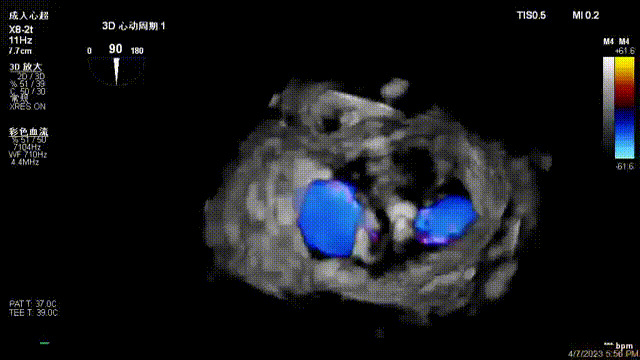

出院前隨訪超聲